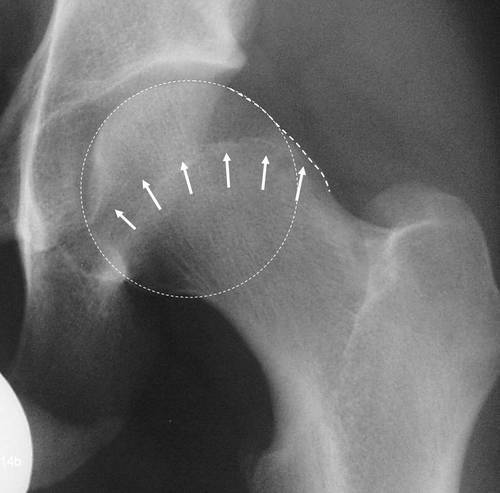

股骨髋臼撞击症

股骨顶部(股骨头)呈圆形,像一个球,位于窝状的髋臼内

髋臼股骨撞击征髋臼盂唇损伤的x光评价